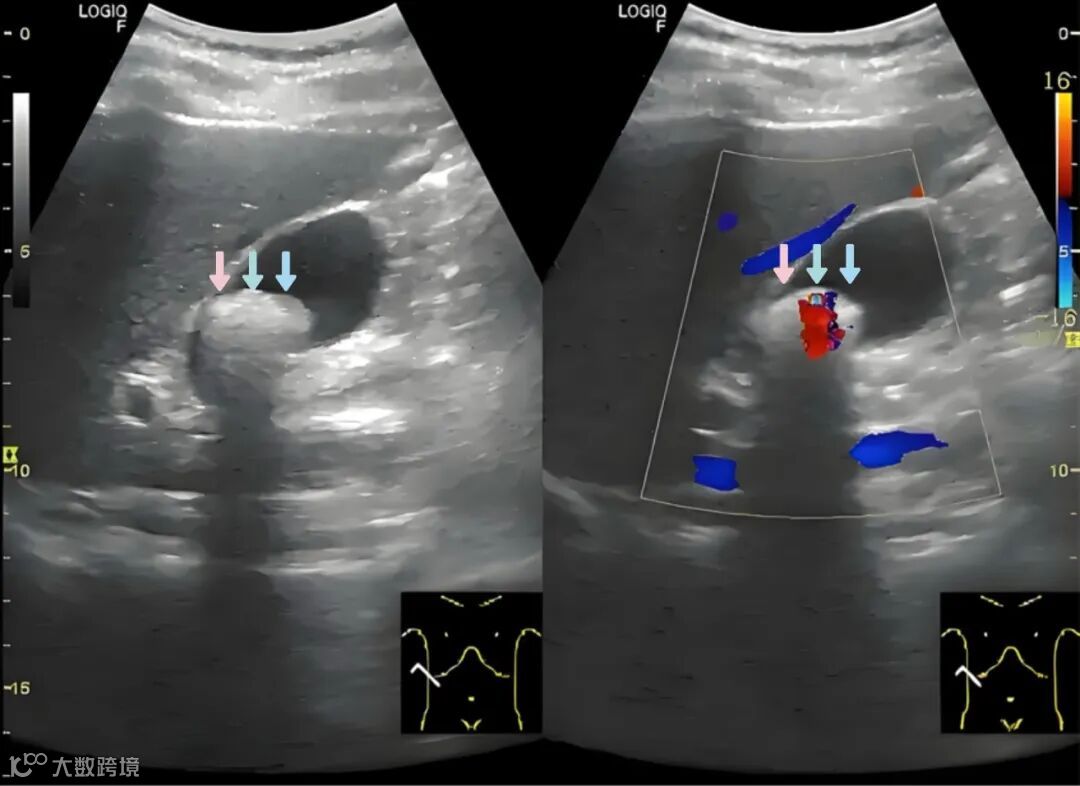

该药物主要是指头孢曲松钠,在体内不能被分解代谢,一部分经肾脏排出,剩下的以原型沉积于胆汁内,随胆汁一起排出。正常情况下,在饮食前,胆汁大部分储存于胆囊内,进食后随着胆囊收缩胆汁逐渐排出,但由于患者在治疗期间,饮食量减少且以清淡为主,胆汁排出减少,导致胆囊内胆汁淤积,头孢曲松钠在胆汁中的浓度逐渐增高,超过饱和度后,头孢曲松钠与胆汁中的钙盐成分结合,从而形成短暂性的胆囊结石,此时超声检查的话,即可探及胆囊腔内的强回声团。随着药物的停用,胆汁内头孢曲松钠浓度的减低,与钙盐结合的头孢曲松钠又重新溶解于胆汁内并随胆汁排出,此时胆囊腔内的强回声团也随之消失。

声像图显示的结石状态、大小及数量变化较大,出现“三快”征象,即结石形成快、碎解快、消失快;